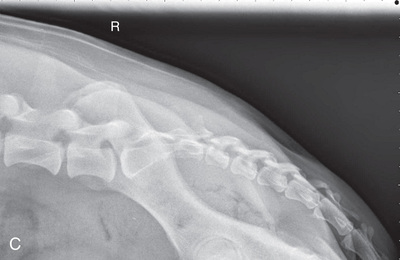

High-quality images are needed to see subtle changes in bone opacity, shape, and angulation of the vertebrae or vertebral column1,2 (Table 20.1). The common views of this portion of the axial skeleton are the lateral (L) and ventrodorsal (VD) views of the cervical, thoracic, thoracolumbar, lumbar, lumbosacral, sacral, and caudal vertebrae. Depending on the size of the patient, a full survey study is either four or five images of each orthogonal view.

MEASURE: Across the shoulder at the level of C6 to ensure adequate penetration of the caudal cervical vertebrae. Overexposure may occur with the cranial cervical vertebrae. Coned-down views can be made of these areas.

CENTRAL RAY: C3 to C4.

BORDERS: Base of the skull to the spine of the scapula (just past the shoulder joint, about T2, to include the cervical vertebrae). Collimate tightly to the edge of the wings of the atlas and the center of the spine of the scapula.